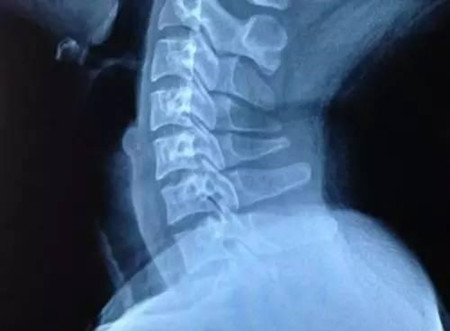

如今提起頸椎病,年輕人再也不能充耳不聞,因?yàn)榻鼛啄瓯活i椎病迫害的年輕患者越來越多,而且癥狀都普遍較重。因此,年輕人必須從現(xiàn)在開始著手了解頸椎病的病因,然后展開針對(duì)性地預(yù)防和改善。

1.長(zhǎng)期伏案工作:由于現(xiàn)在的工作大多數(shù)都需要借助電腦,所以,很多職業(yè)的年輕人一天中大約有8個(gè)小時(shí)都是在伏案狀態(tài)。而一旦工作繁忙,就很少有時(shí)間能活動(dòng)頸椎,如此下去頸椎會(huì)長(zhǎng)時(shí)間處在前屈狀態(tài),周圍的肌肉也得不到放松,從而易形成慢性勞損,繼而誘發(fā)頸椎病。

2.缺乏必要活動(dòng):下班之后本應(yīng)該好好放松一下,但是很多年輕人卻還是拿著手機(jī)玩游戲或窩在床上用電腦看電影。這會(huì)讓本來就勞累一天的頸椎變得更加僵硬不適,時(shí)間一長(zhǎng)自然會(huì)加速頸椎的老化,增加患頸椎病的風(fēng)險(xiǎn)。

一旦出現(xiàn)了頸椎病,絕大多數(shù)患者經(jīng)非手術(shù)改善能夠緩解癥狀甚至治愈不復(fù)發(fā)。中藥外貼療法是大家最常用的改善方法,針對(duì)無菌炎癥效果最好,無痛苦、無并發(fā)癥、安全快捷、改善肯定等一系列優(yōu)點(diǎn),如王九正貼,更多健康咨詢關(guān)注微信whk2969